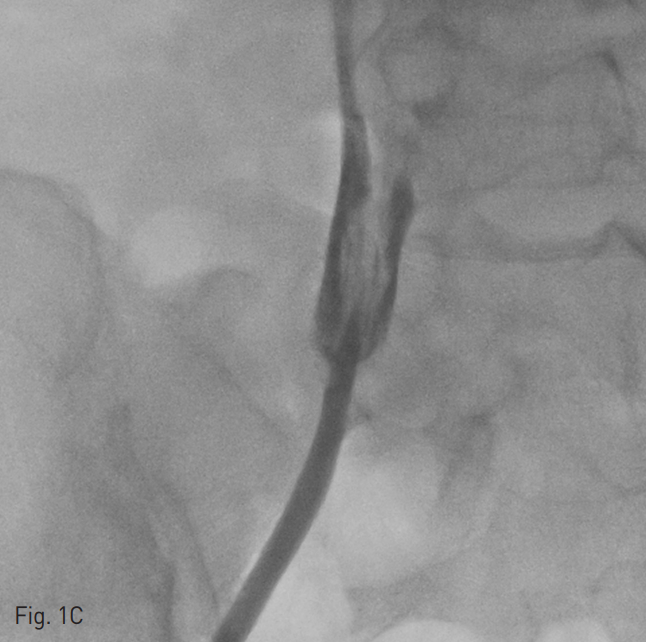

양측 내경정맥을 통한 정맥 조영술에서 상대정맥이 완전히 폐색되어 있으며 (Fig. 1A-B) 이를 대체하기 위해 우측 대퇴정맥에 투석용 카테터를 삽입하였지만 이 또한 10일 후 카테터 주변으로 혈전이 발생하였다(Fig 1C). 이어서 허리 경유 접근을 통해 투석용 카테터 삽입을 위해 하대정맥 천자를 시도하였으며 6 Fr sheath까지 들어간 후에 천자된 곳이 대동맥임을 알게 되어 대동맥에 stent-graft를 넣었다 (Fig. 2A). 투석이 급하여 일단 간정맥을 통하여 투석용 카테터를 삽입하였으나 (Fig. 1D) 이 역시 혈전으로 인한 기능 부전으로 수 차례 교환술을 시행하였다.

Fig. 1. Diffuse venous thrombosis of both internal jugular and femoral veins.

C. Venogram through the right femoral vein shows filling defect suggesting thrombus at tip of tunneled dialysis catheter in the right femoral vein after 10 days of catheter displacement.